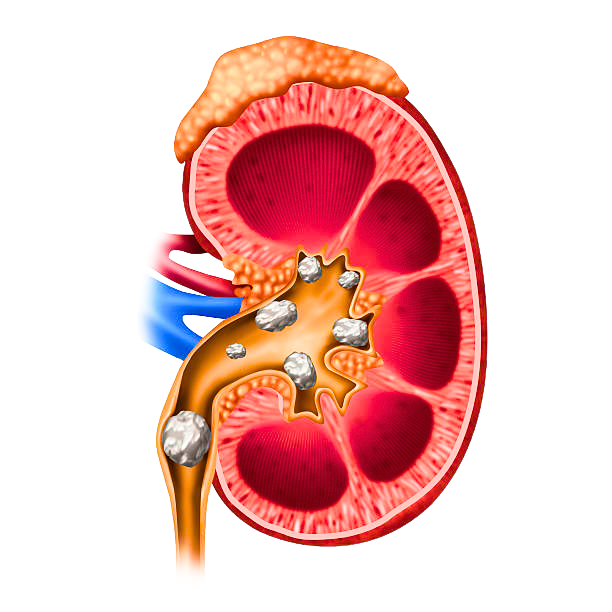

kidney

stones cure